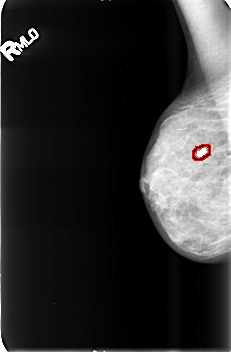

FILE: B_3428_1.RIGHT_CC.OVERLAY

TOTAL_ABNORMALITIES 1

ABNORMALITY 1

LESION_TYPE CALCIFICATION TYPE COARSE DISTRIBUTION N/A

ASSESSMENT 2

SUBTLETY 5

PATHOLOGY BENIGN_WITHOUT_CALLBACK

TOTAL_OUTLINES 1

BOUNDARY